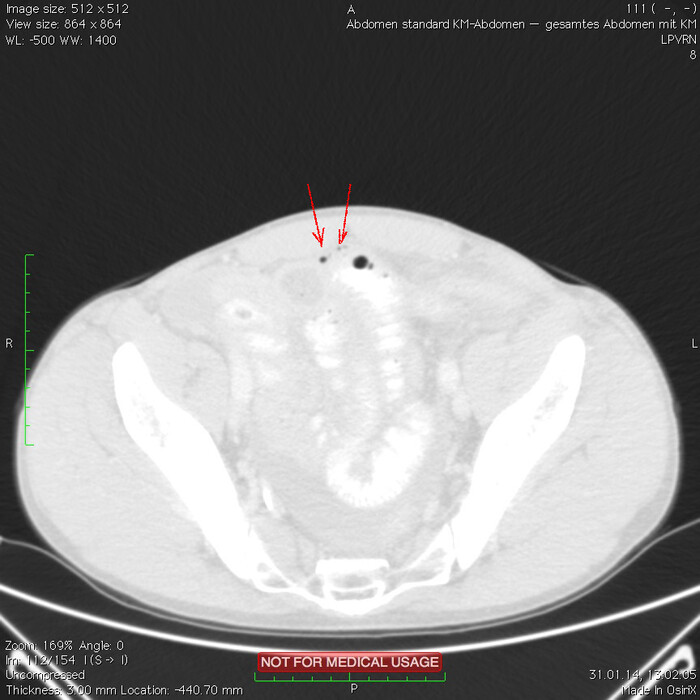

Мужчина, 32 года. Во время игры в футбол получил удар в низ живота, игру продолжил. Впоследствии боли в животе усиливались, стали нестерпимыми, ухудшилось общее самочувствие. На следующий день после игры пошёл сдаваться в больницу. Хирурги клинически описывают разлитой перитонит (воспаление брюшины) и отсылают пациента к нам на КТ, которое мы провели с внутривенной дачей контраста + заставили контраст ещё выпить (специальный раствор для перорального применения).

Так как клиника у нас острого живота после тупой травмы, учитывая что боли во всём животе и признаков большой кровопотери нет, то первое, что ищем - это свободный газ в брюшной полости, и находим его! (для этого лучше всего подходит т.н. лёгочное окно, как представлено ниже, или можно искать в костном окне - это спец.настройки яркости и контраста для просмотра разных структур тела - лёгкие, мозг, мягкие ткани, кости):

Отмечаем про себя, что в верхних квадрантах свободного газа не так уж и много. При перфорации желудка газа намного больше. Также выясняем, что газ есть также и в нижних квадрантах: